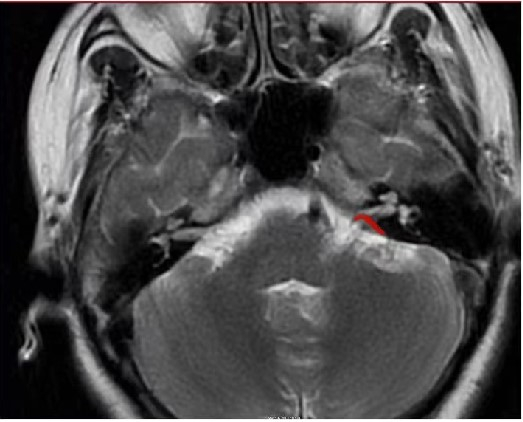

▲影像学检查(图片中标红部位为责任血管位置)

据神经外科主任李栋良介绍,微血管减压术是医学界公认的根治面肌痉挛的方法,该手术技术成熟,风险较小,效果很好且立竿见影。简单地说,通过锁孔微创手术寻找到压迫面神经的责任血管,分离责任血管,插入一块垫片,从而实现对压迫神经的减压。该手术不仅可以根治面肌痉挛,也是治疗三叉神经痛的优先推荐方法。其优点在于,可在解除局部血管压迫的同时,保留三叉神经感觉传导的完好,也不会出现面部感觉的丧失。

同时李栋良提醒广大患者:“特发性面肌痉挛一旦确诊,微血管减压术是首选治疗方法。通常药物治疗无效,局部注射肉毒素容易复发且可能造成不可逆的面瘫。”(文/徐晓月;图/綦江区人民医院)